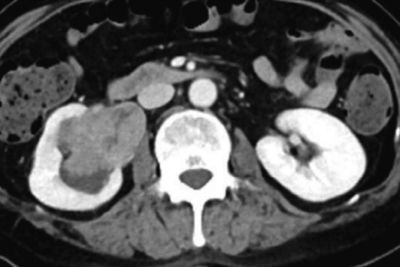

尿所見:蛋白1+、糖(-)、潜血3+、沈渣に赤血球多数/1 視野、白血球2〜5/1 視野。尿細胞診はクラスⅤ。血液所見と血液生化学所見とに異常を認めない。胸部エックス線写真で異常を認めない。腹部造影 CT の水平断像と冠状断像とを別に示す。全身検索でリンパ節転移と遠隔転移とを認めない。膀胱鏡検査で異常を認めない。尿管鏡による生検で高異型度尿路上皮癌の細胞を認める。